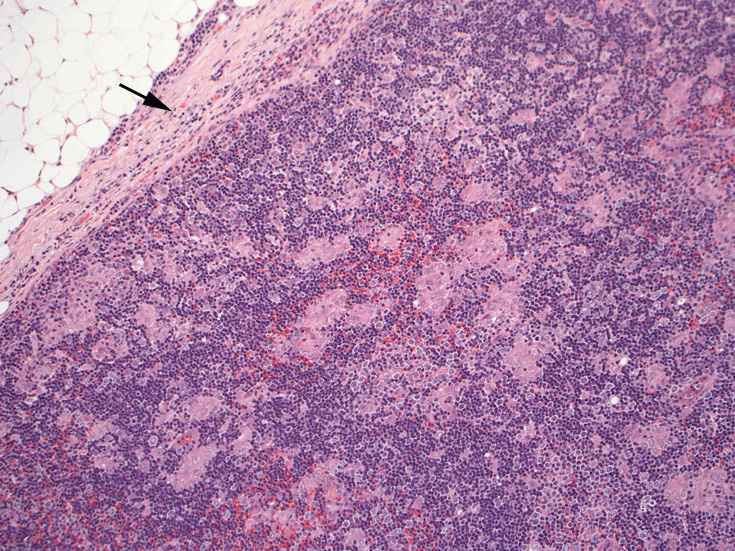

リンパ節病理組織所見

通常傍濾胞領域に小型, 不整形の類上皮細胞肉芽腫が多数形成されている。この症例では慢性炎症を伴い線維性に肥厚した皮膜直下にも多くの肉芽腫病変が散在する。Piringer型リンパ節炎と呼ばれる。

リンパ節病変にトキソプラズマ嚢子は確認できないことがほとんど

皮質から傍皮質に肉芽腫が散在大小不整な肉芽腫looseな肉芽腫皮膜下にも肉芽腫あり